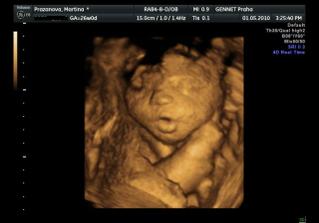

Určitě dám sem vědět i s aktuální fotečkou. Jména mám v pase. A 1.května jdeme na 4D UTZ, tak se moc těšíme 🙂

Letí to jak blázen, vždyť to znáš 🙂. Zatím nevíme nic, ale zítra jdeme na velký genetický UTZ, tak snad tam prcek nebude sedět v tureckém sedě jako minule 🙂))